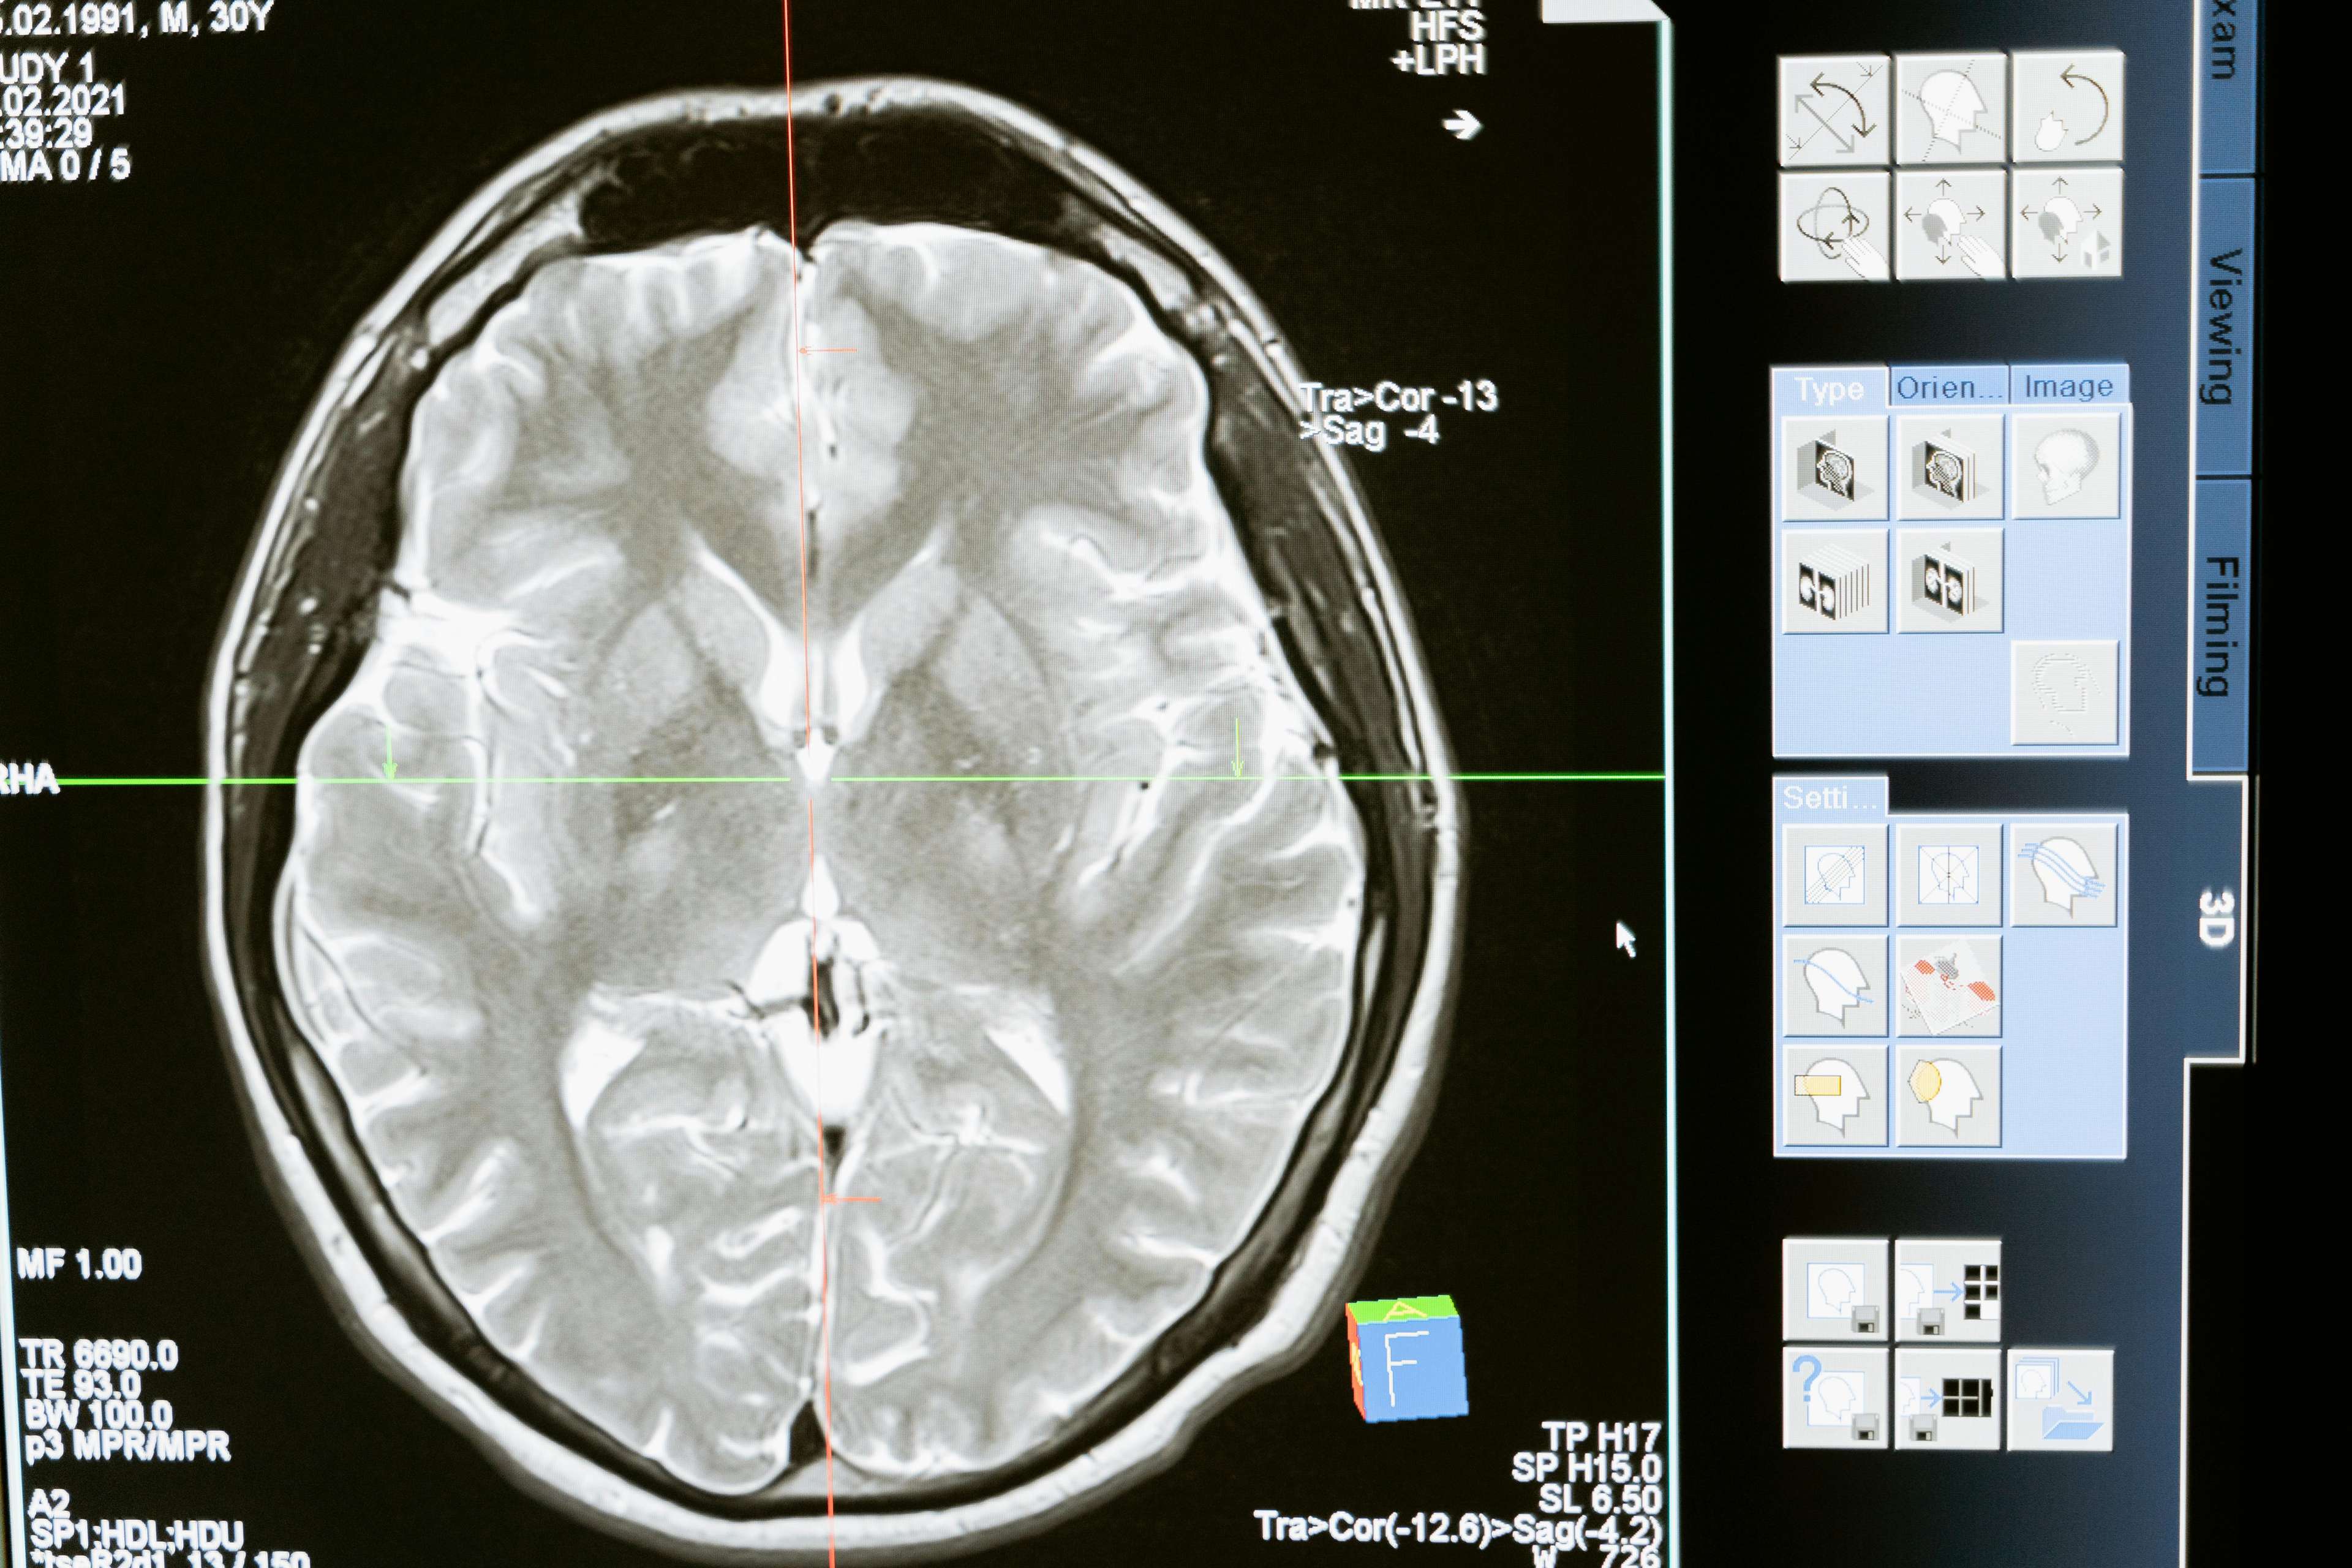

Stimulasi Otak Dalam (DBS) adalah prosedur pembedahan yang melibatkan menanamkan peranti yang menghantar impuls elektrik ke kawasan tertentu otak. Teknologi ini telah wujud selama beberapa dekad, tetapi penemuan terbaru telah menjadikannya lebih berkesan, mudah diakses dan selamat. Pada masa lalu, DBS digunakan terutamanya untuk merawat gangguan pergerakan seperti Parkinson, Dystonia, dan Essential Tremor. Walau bagaimanapun, aplikasinya telah berkembang untuk merangkumi keadaan psikiatri seperti gangguan obsesif-kompulsif, kemurungan utama, dan juga sakit kronik. Prosedur ini melibatkan menanamkan elektrod di dalam otak, yang disambungkan ke peranti seperti alat pacemaker yang menghasilkan impuls elektrik. Impuls ini mengawal aktiviti otak yang tidak normal, mengurangkan gejala dan meningkatkan kualiti hidup.